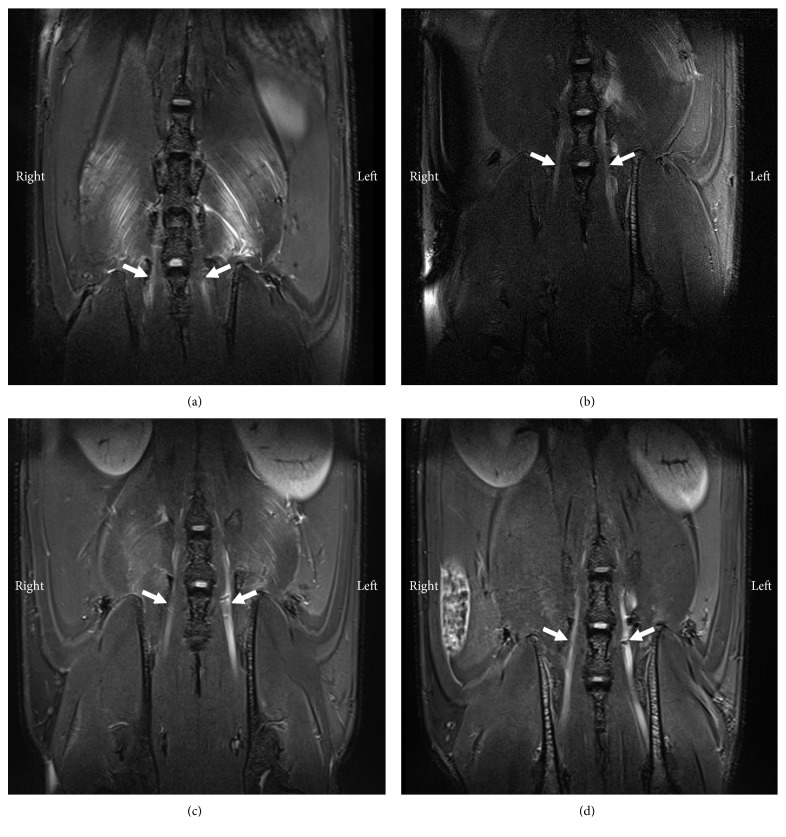

3.5. Low MR Signal Observed at the Site of Ligation

In uninjured left and right L5 spinal nerves, the MR signal was slightly hyperintense to the surrounding soft tissue. In comparison, the left L5 spinal nerves of SNL rats were much brighter, and hypointensive areas were observed at the approximate site of ligation (Figure 6). After these rats were terminally perfused, histology of harvested spinal nerves confirmed the presence of iron in injured nerves only (Figure 7). This result suggests that MR signal increase in left L5 spinal nerves of SNL rats is due to ligation and that surgical removal of the left L5 spinus process or the L5 laminar bone did not damage nerves. Moreover, it suggests that only injured nerve tissues would cleave and absorb sufficient MMP-12-targeted IONPs, to cause MR signal decrease.

Figure 6.

Coronal T2-WI a day after intrathecal injection of MMP-12-targeted probe. White arrows indicate left and right L5 spinal nerves, in sham and SNL rats (n=2 per group). Compared to uninjured nerves, injured nerves are enlarged, and iron-induced signal loss is observed at the approximate site of ligation. (a) Sham 1. (b) Sham 2. (c) SNL 1. (d) SNL 2.